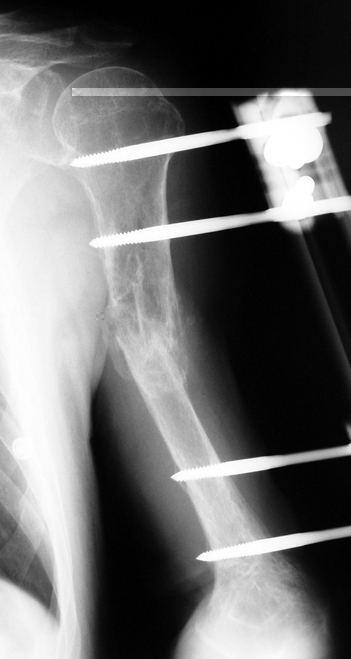

Humerus Psödartroz

Pseudarthrosis

Pseudarthrosis of fracture and pseudarthrosis treatment is currently important problem for orthopedic surgery. Various treatment modalities have been described for pseudarthrosis treatment. All of the treatment methods include high complication rates and additional problems. Leg-length discrepancy, deformity and soft-tissue loss and chronic infection can concomitance with pseudarthrosis. Many internal or external fixation techniques have been described for pseudarthrosis. Debridement and resection of bone fragment from the pseudarhtosis area vascularized or nonvascularized fibula graft, vascularized muscle flaps, bone grafting followed internal fixation techniques make a option for treatment of pseudarthrosis treatment. But these treatment modalities may not correct deformity and leg-length discrepancy. Recently, ilizarov techniques which is basis depend on distraction osteogenesis , bone segment transport or acute shortening after the resection at the site of pseudarthrosis combined with lengthening at another level of bone have been used. These treatment techniques may include some advantage for problems of infection, leg-length discrepancy, soft-tissue loss, and joint contracture.